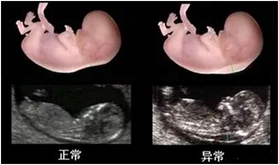

2、胎兒系統(tǒng)超聲檢查(四維大排畸:22-26周)

除了常規(guī)檢查以外,尚需要進(jìn)行系統(tǒng)全面的胎兒超聲檢查,俗稱“大排畸”,以全面了解胎兒的生長發(fā)育情況。